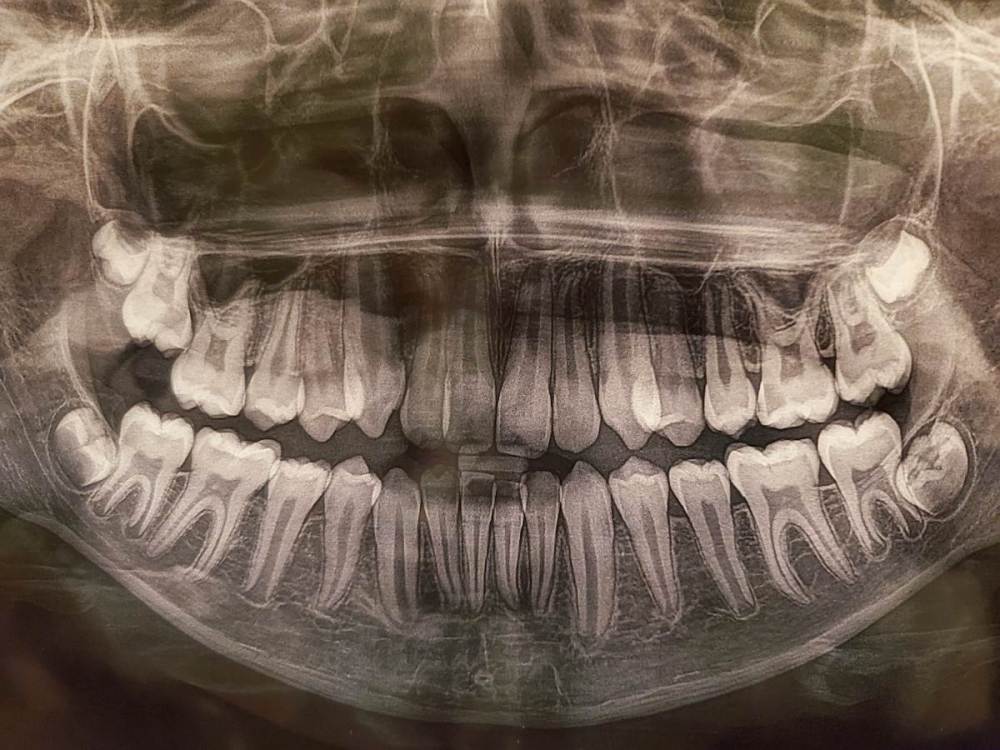

Sapfir Опубликовано 26 августа, 2021 Поделиться Опубликовано 26 августа, 2021 (изменено) Здравствуйте! Ребенку 11 лет, зубы начали налазить друг на друга. Хотим выправить, но брекеты рекомендуют с 13 лет. Что посоветуете в этом случае? Фото прикрепил. Изменено 26 августа, 2021 пользователем Sapfir Добавил дополнительное фото Ссылка на комментарий

St. Опубликовано 26 августа, 2021 Поделиться Опубликовано 26 августа, 2021 Добрый день. Сходите к еще одному ортодонту на консультацию послушать альтернативное мнение. Я бы не откладывала лечение на 2 года, тем более что справа 7 сам без помощи ортодонта не прорежется и после формирования корня вытягивать его будет сложнее. Помимо этого скорее всего нижние зубы мудрости нужно будет удалять не дожидаясь их полного формирования, т.к. они уже упираются в соседей и дальше будет сложнее. Еще обратите внимание на боковые зубы - по снимку там вероятен кариес 16,26 зубов, но нужно посмотреть очно в скольки зубах он есть (не все кариесы видно на снимках) 1 1 Ссылка на комментарий